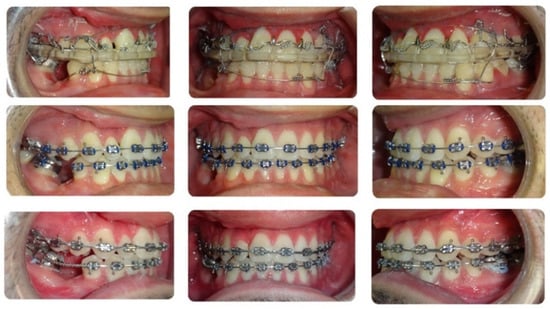

2. Case Description

3.1. Step 1: Virtual Orthodontic Setup

3.2. Step 2: Virtual Surgical Repositioning

3.3. Step 3: Reverse Engineering the Transitional Occlusion